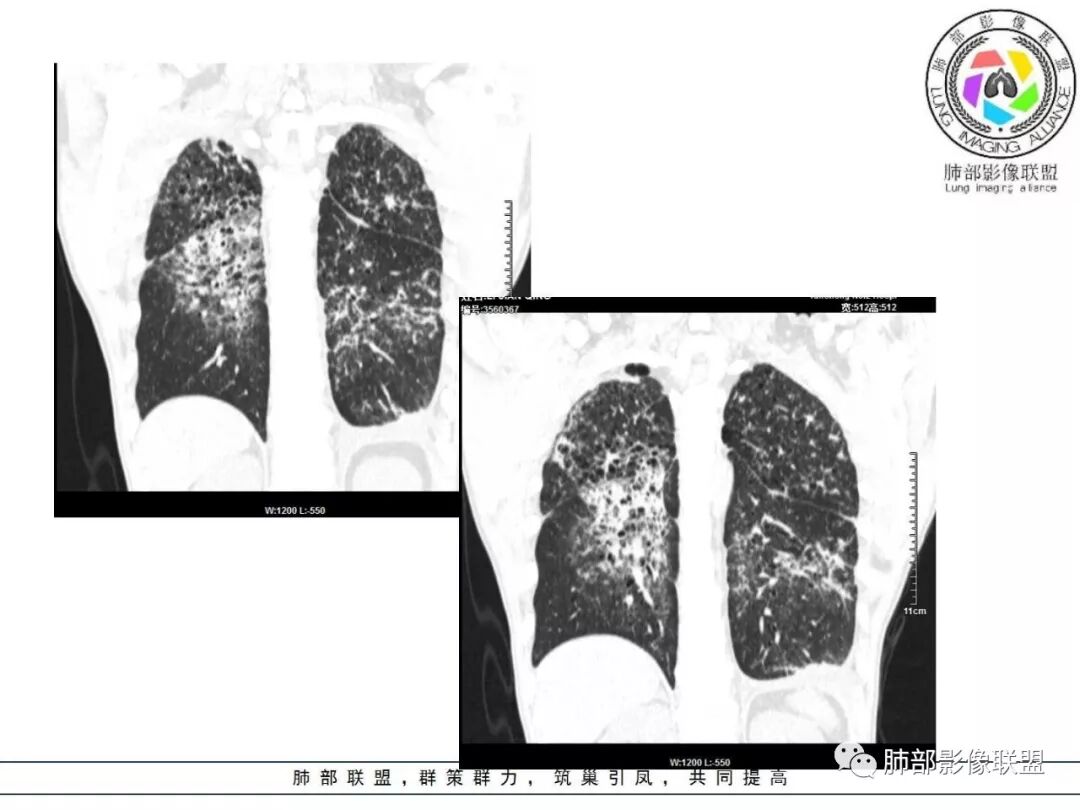

双肺间质性病变,中央间质增厚,胸膜下间质增厚,左侧胸膜肥厚,胸廓变小,肋间隙变窄。

患者双上肺弥漫性改变,小叶间隔增厚,中央轴为主,胸膜下少量,感染为主,鉴别结核。

病变一般沿血管支气管束分布或小叶分布,一般上肺多于下肺(这与常见继发性肺结核分布相若)。

2. 肺气肿背景(小叶中心性肺气肿);双肺多发病灶整体沿血管支气管束及胸膜下分布,以上叶及下叶背段分布为主,有实变及GGO,边界清楚,有树芽,小叶间隔及中央间质增厚,叶间裂见到多发结节,部分支气管不规则牵拉扩张,提示病灶纤维化明显,结合临床病史,考虑病灶为间质性感染,肺门及纵隔内有钙化淋巴结,小叶间隔结节,考虑淋巴道增值性疾病可能,综合常规要怀疑间质性肺结核。

3.  该病例临床提示感染,有支气管扩张,提示纤维化,需要与感染后的OP鉴别,但是OP病灶常无结节感;间质性肺结核有时与不典型结节病鉴别也比较困难,结节病常以双肺门淋巴结增大为特征。临床上结核发病率较高。